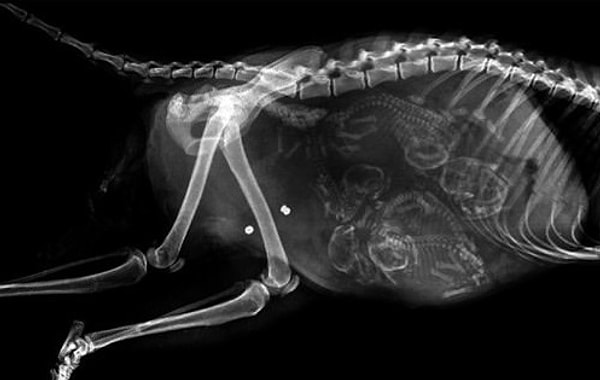

1. Змея